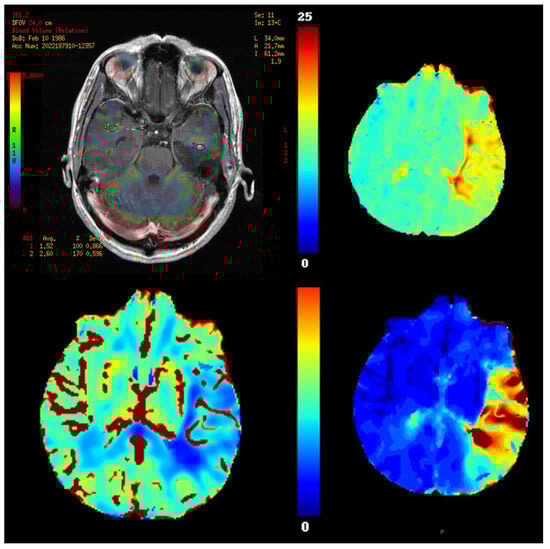

11. Perfusion Imaging

11.1. Physics and Signal Model

11.2. Acquisition and Key Parameters

11.3. Outputs and Units

11.4. Validation and Quantification Considerations

11.5. Clinical Applications

- Tumor grading and characterization,

7.3. Outputs and Units